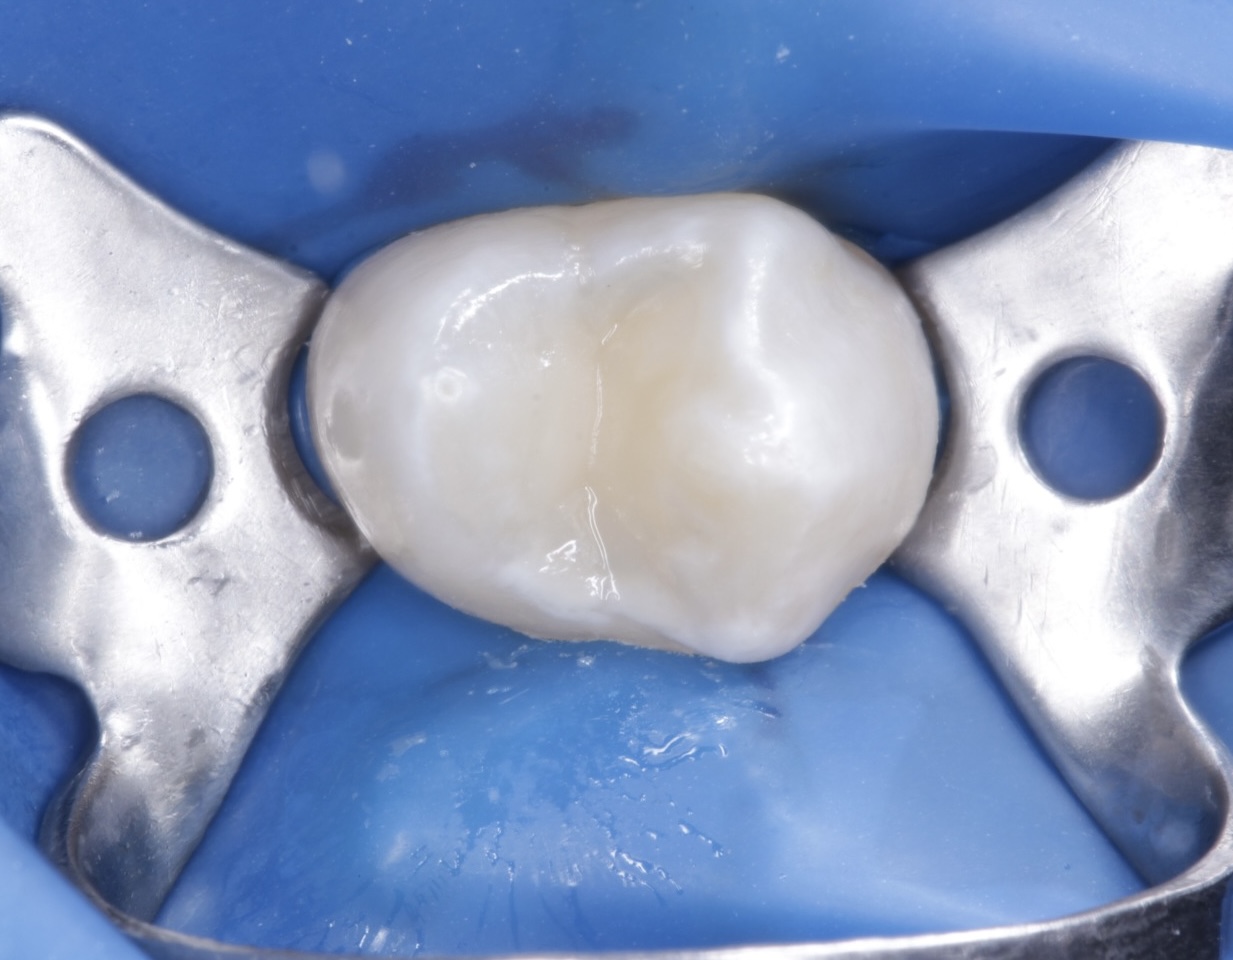

Детский и подростковый врач-стоматолог, терапевт